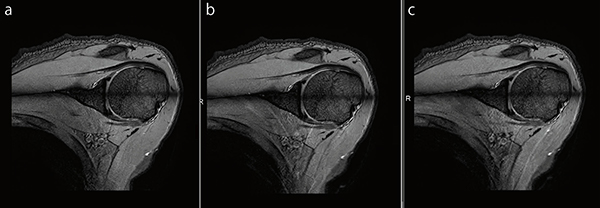

●肩関節Radial Stack T2*WI

図8 aは,IP-RAPIDを使用していない画像です。それに対して図8 b,cは,IP-RAPIDを使用し,撮像時間の短縮を図っています。

図8 肩関節Radial Stack T2*WI

a:IP-RAPID off, Phase=1.2, Freq/Phase=224×224, scan time=3:08

b:IP-RAPID on, Phase=1.5, IP-Recon=Light, Freq/Phase=224×224, scan time=2:31

c:IP-RAPID on, Phase=2.0, IP-Recon=Medium, Freq/Phase=224×224, scan time=1:54